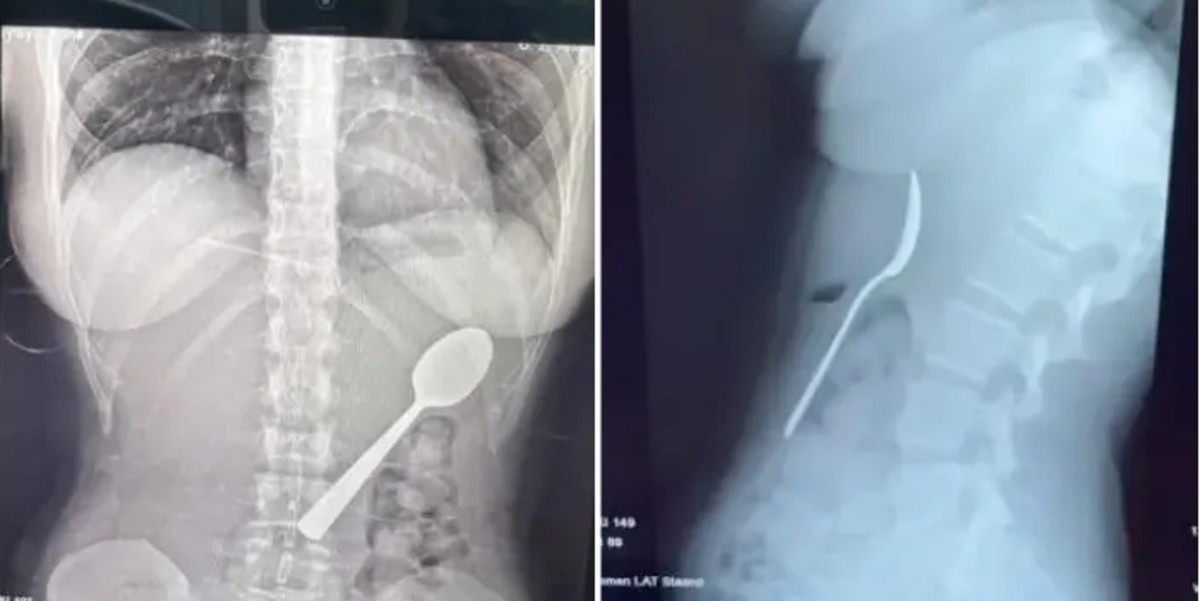

벨기에에서 반려견의 갑작스러운 행동으로 인해 여성이 17㎝ 길이의 숟가락을 삼키는 위험한 사고가 발생했습니다. 이 여성은 자신의 엑스레이 사진을 공개하며 비슷한 사고 예방을 당부했습니다.

하지만 저녁 식사 후 상태가 악화되면서 그는 응급실을 찾을 수밖에 없었습니다. 병원에서 촬영한 엑스레이 사진에는 뱃속에 수직으로 세워진 채 걸려 있는 숟가락이 선명하게 나타났습니다. 의료진은 숟가락이 너무 커서 자연 배출이 불가능하다고 진단했습니다.

그는 경각심을 위해 문제의 숟가락을 기념품으로 보관하기로 결정했습니다. 아멜링크스씨는 "유쾌한 경험은 아니었지만 수술 결과가 나왔을 때 정말 안도했습니다"라며 "수술 다음 날 평소처럼 출근했는데, 동료들은 엑스레이 사진을 보기 전까지 제 말을 믿지 않았습니다"라고 말했습니다.